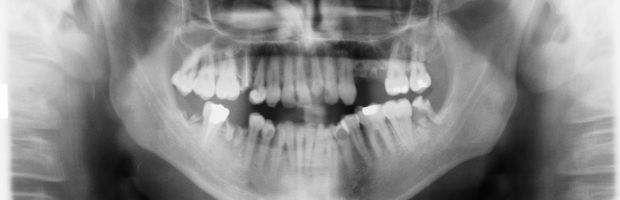

Dental X-Rays

Dental radiographs (x-rays) are essential, preventative, diagnostic tools that provide valuable information not visible during a regular dental exam. Dentists and dental hygienists use this information to safely and accurately detect hidden dental abnormalities and complete an accurate treatment plan. Without x-rays, problem areas may go undetected.

Dental x-rays may reveal:

Detecting and treating dental problems at an early stage can save you time, money, unnecessary discomfort, and your teeth!